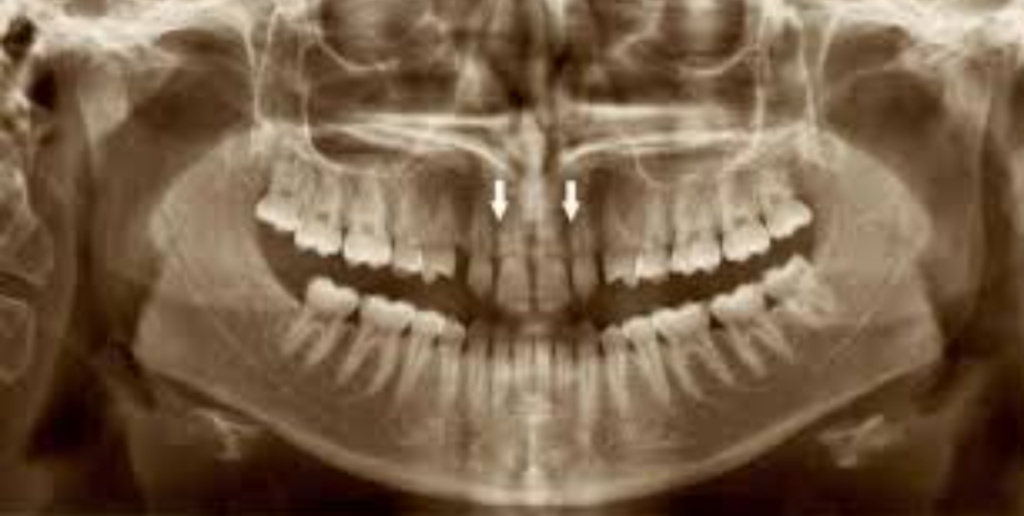

Les agénésies dentaires, définies comme l’absence congénitale d’une ou plusieurs dents, posent des défis cliniques complexes nécessitant une approche multidisciplinaire. Ce document explore de manière détaillée les options thérapeutiques pour le traitement des agénésies, en mettant l’accent sur les incisives latérales supérieures et les deuxièmes prémolaires inférieures. Les choix thérapeutiques dépendent de nombreux facteurs, incluant la morphologie dentaire, les relations occlusales, les conditions parodontales, et les considérations socio-économiques. Les traitements orthodontiques et prothétiques sont souvent combinés pour obtenir des résultats fonctionnels et esthétiques optimaux.

Agénésies des Incisives Latérales Supérieures

Agénésies des Deuxièmes Prémolaires Inférieures

Traitement des Agénésies Bilatérales